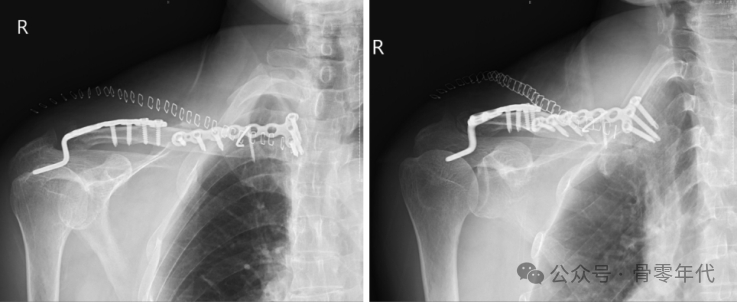

一名62岁的女性在当地医院接受了内侧和远端固定。她经历了持续的锁骨内侧突出和疼痛,术后1个月(A)后前位X线片和(B)三维CT显示锁骨内侧骨片再次移位。她接受了翻修手术,包括移除最初的植入物并用锁骨钩钢板固定。在6个月的随访中,患者显示胸锁关节和肩锁关节的X线片是一致的。